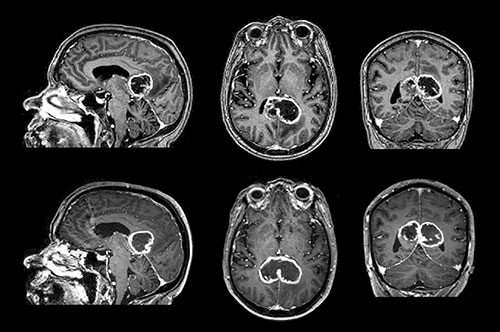

A butterfly glioma is a glioma that involves both cerebral hemispheres by growing through the corpus callosum, the white matter tract that crosses the midline of the cerebrum. The result when the tumour grows symmetrically in the two hemispheres is the characteristic image reminiscent of a butterfly. Differential diagnoses of butterfly lesions in the corpus callosum are lymphoma of the central nervous system, tumefactive multiple sclerosis and toxoplasmosis.

The figure shows contrast-enhanced T₁-weighted MRI images of a butterfly glioma with strong peripheral contrast enhancement and central necrosis, typical of a glioblastoma. Butterfly gliomas most frequently infiltrate the genu of the corpus callosum (≈ 60 %), and less often the body (≈ 30 %), and splenium (≈ 10 %) (1). Symptomatically, such tumours may result in disconnection syndromes such as alexia, agraphia and apraxia, rather than ordinary sensomotoric deficits. For example, unilateral apraxia may occur if the language areas in the left hemisphere are disconnected from the motor areas in the right hemisphere. Instructed verbally to perform tasks, the patient will be unable to perform them with his left hand, but able to perform them with his right hand.

The lower part of the figure shows the same tumour after 16 days, where it has grown from 27.4 cm³ to 37.6 cm³, a 37 % increase in volume. This translates into a doubling time of 32 days, assuming exponential growth. There are few systematic in vivo studies in the literature of glioblastoma growth rates and doubling times. The few existing studies estimate doubling times at from 10 to 95 days.